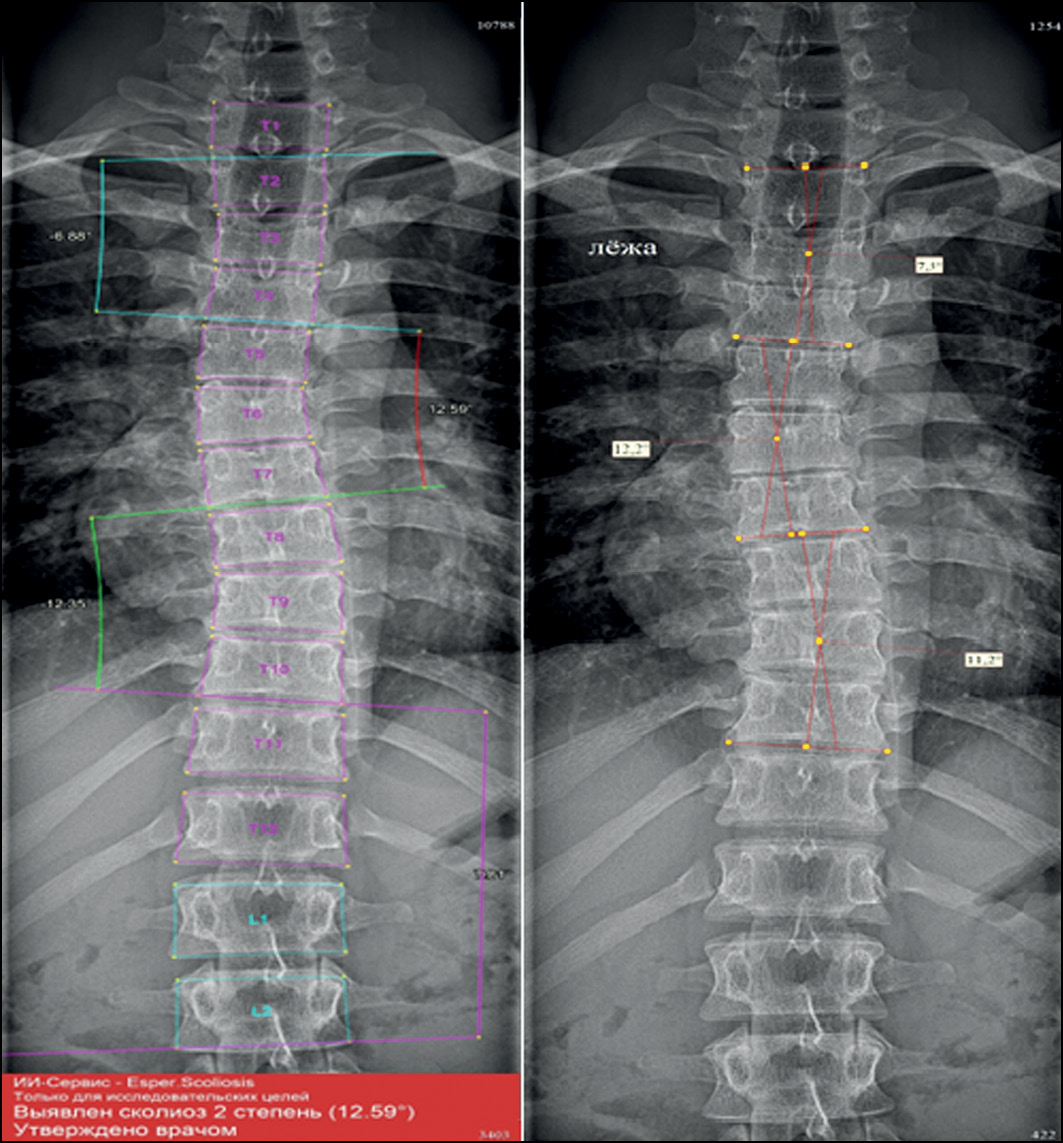

The bulk of this work was performed in a hospital where adolescents are screened for scoliosis, as part of multiple examinations for medical commissions, to determine whether adolescents match the criteria for army enlistment. Thus, radiographs in test set 1 and test set 2 were divided according to the severity classification included in Federal Law No. 565, where any small curves with angles <10° are considered grade 1 scoliosis [16]. The new automatic system for evaluating scoliosis on digital radiographs can help radiologists to define the scoliosis grade and measure the curve’s angle, particularly in situations such as screening for scoliosis and at times of heavy workload in outpatient clinics. In these situations, radiologists can use the program as an objective tool, increasing the accuracy of scoliosis evaluation on frontal radiographs because the interobserver variability can be avoided if radiologists use the same instrument. Moreover, it can significantly save the radiologist’s time. In addition, Cobb’s angles measured by the system were acceptable, with no significant clinical variability in most of the evaluated curves. Fig. 4 shows an example of how the system works.

Fig. 4. X-ray image showing grade 2 scoliosis. Analysis by the system (left) and by the radiologist (right). The radiologist did not measure the thoracolumbar curve as the lower EV is not shown in the image.